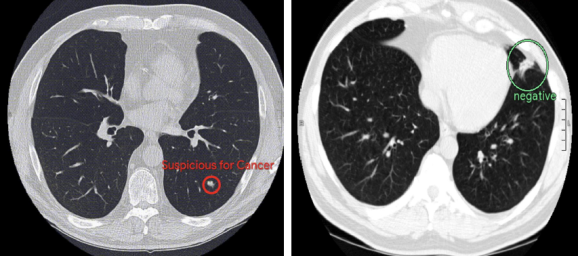

En este sentido y tal y como informan en Venture Beat, desarrolladores de IA de Google junto a investigadores del centro médico Northwestern Medicine habrían conseguido entrenar un modelo de Inteligencia Artificial capaz de detectar el cáncer de pulmón a partir de esáneres de imagen, con una precisión superior a la mostrada por un grupo de radiólogos con más de 10 años de experiencia en este campo.

A la hora de analizar una única imagen, el modelo desarrollado por los ingenieros de Google superó en un 5% la capacidad humana a la hora de detectar un caso de cáncer, dejando en «evidencia» a un equipo de expertos formado por nada menos que seis personas. Por otro lado, lo nuevo de AlphaGo también ha demostrado su pericia a la hora de descartar falsos positivos, superando en este caso a sus «compañero humanos» en un 11%.

Los resultados de este estudio, publicados en la revista Nature Medicine muestran además cómo la inteligencia artificial, utilizando un sistema de aprendizaje profundo, es capaz de predecir si un paciente tiene cáncer de pulmón (generando un índice de riesgo de padecerlo) e indentificar la presencia del tejido maligno en los pulmones.

Tal y como ha explicado Shravya Shetty, director técnico del proyecto, «El sistema de IA utiliza el aprendizaje profundo volumétrico 3D para analizar la anatomía completa en las tomografías computarizadas de tórax, así como algoritmos basados en técnicas de detección de objetos que identifican regiones con lesiones malignas».